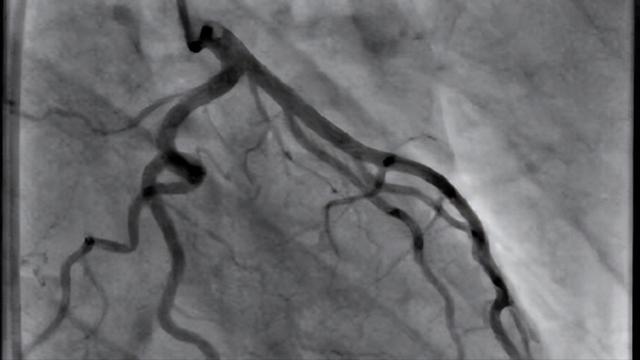

上面提到的檢查都是比較初級(jí)的器械檢查,可以說血脂高的人都能做一下檢查。但是,在現(xiàn)實(shí)臨床上還有一些檢查是專科檢查,對(duì)于一些高度患者存在冠心病和腦血管疾病的人可以考慮。比如說有些高脂血癥患者,就像我開篇所說的那位朋友,長(zhǎng)時(shí)間血脂高沒有管理,任由其升高,結(jié)合臨床評(píng)估還是一個(gè)冠心病高危人群,這時(shí)候?yàn)榱嗣鞔_其是不是有冠心病,就有可能需要進(jìn)一步檢查運(yùn)動(dòng)平板心電圖、負(fù)荷狀態(tài)下的心臟彩超、心肌核素顯像、冠脈CTA,甚至心肌缺血癥狀典型的人可以直接考慮做冠脈造影明確是都存在冠狀動(dòng)脈的病變。

冠脈造影圖像